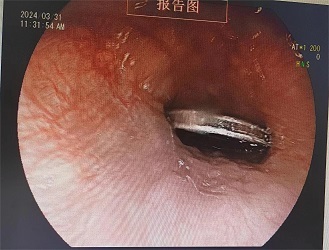

鉴于淘淘年龄太小,无法配合普通的胃镜检查,杨文智与儿科副主任医师周俏滢(佛山市南海区人民医院帮扶专家)共同商讨后,决定采用无痛胃镜下异物取出术。这一方案能最大程度地减轻淘淘的痛苦,缩短取异物的时间,并提高取出的成功率。

经过完善的术前检查,手术迅速展开。杨文智熟练地操控胃镜,仅用5分钟就成功用异物钳取出了硬币。从淘淘就诊到异物取出,用时不到2小时,充分展现了榕江县人民医院多学科合作的优势。